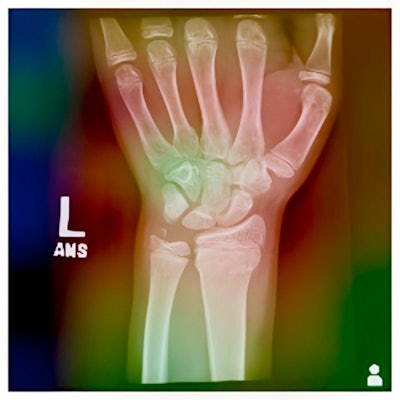

Grad-CAM heatmap of the EfficientNet-B2 model for a sample radiograph.Grad-CAM heatmap of the EfficientNet-B2 model for a sample radiograph.Journal of the Pediatric Orthopaedic Society of North AmericaThe best model was EfficientNet-B2, according to the findings, which achieved a validation accuracy of 84% and a test accuracy of 84% in identifying physeal fractures. The model had high precision (81%), recall (89%), and F1-score (0.86) on the test set.

In addition, to interpret the model's predictions, the researchers used Grad-CAM, a technique that visualizes the regions of the radiographs that the model learned to focus on for classification.

“Fine-tuning an EfficientNet model can achieve high accuracy in identifying physeal fractures. Further, Grad-CAM provides interpretability and transparency for the model's predictions, highlighting regions of interest and potential sources of error,” the group wrote.